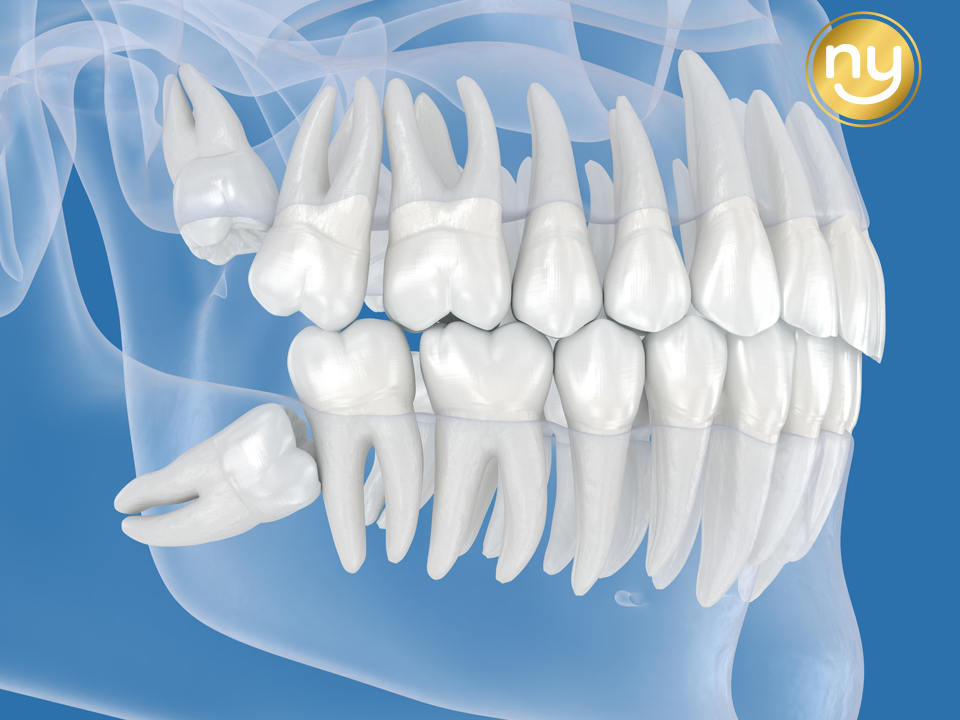

대표적으로 치아가 옆으로 누워

앞 치아를 밀어내는 ‘수평 매복’,

잇몸 속 깊이 전부 묻혀 있는 ‘완전 매복’,

그리고 신경과 가까운 위치에

자리 잡은 경우가 있습니다.

이러한 사랑니는

단순 발치로 해결되지 않고,

잇몸 절개나 치아를 나누는

과정이 필요할 수 있는데요.

특히 신경과 가까운 사랑니는

세심한 접근이 필수적이며,